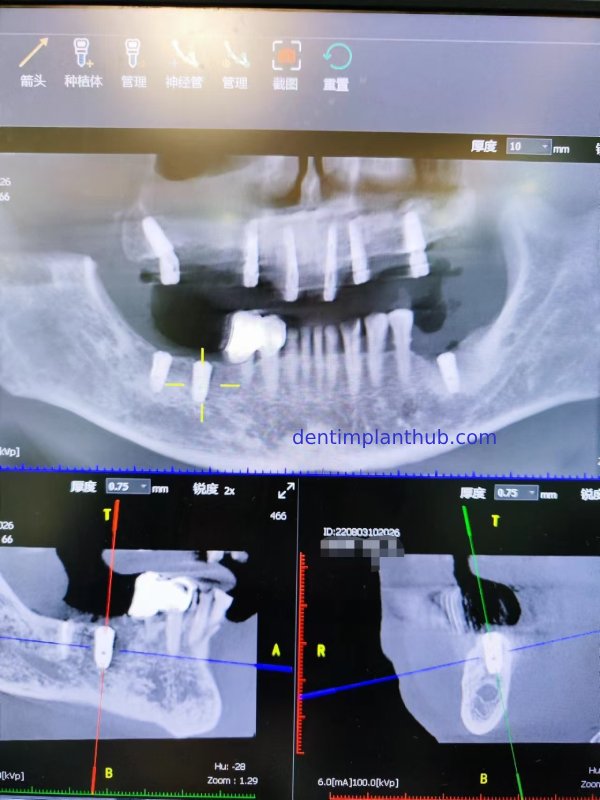

CT screenshots before the surgery and the implant plan

The specific conditions of each tooth position and the implant plan

For tooth 18, with a width of 11.32 and a height of 4.18, an implant with a diameter of 45 and a length of 10 is selected. It needs to be implanted at an inclination. The mesial angle is 49.29°, and a 30° composite abutment is required.

For tooth 16 as an alternative plan, it has a width of 8.08 and a height of 2.95. An implant with a diameter of 5 and a length of 8 is selected. It will be implanted axially. A maxillary sinus floor elevation is required, with 0.5 grams of bone grafting material to be implanted, and a straight composite abutment is needed.

For tooth 14, with a width of 7.03 and a height of 14.13, an implant with a diameter of 4 and a length of 10 is selected. It will be implanted axially. A straight composite abutment is required, with a 15° composite abutment as a backup.

For tooth 12, with a width of 6.24 and a height of 14.95, an implant with a diameter of 3.6 and a length of 12 is selected. It needs to be implanted at an inclination. The buccal angle is 25.35°, and a 30° composite abutment is required.

For tooth 22, with a width of 6.64 and a height of 16.14, an implant with a diameter of 3.6 and a length of 12 is selected. It needs to be implanted at an inclination. The buccal angle is 33°, and a 30° composite abutment is required.

For tooth 24, with a width of 7.01 and a height of 10.24, an implant with a diameter of 4 and a length of 10 is selected. It will be implanted axially, and a straight composite abutment is required.

For tooth 26, with a width of 10.91 and a height of 6.20, an implant with a diameter of 5 and a length of 10 is selected. It will be implanted axially. An internal maxillary sinus lift is required, with 0.5 grams of bone graft material to be implanted, and a straight composite abutment is needed.